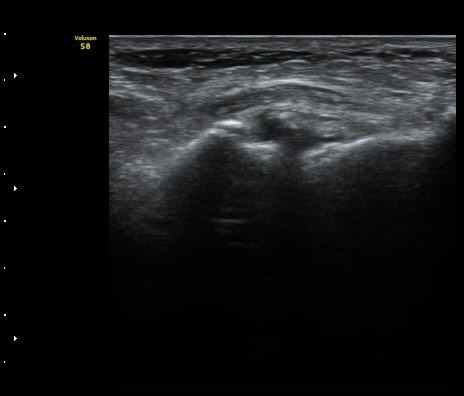

Àδë Á¾°ñºÎÂøºÎ Á¾´Ü¸é°Ë»ç¿Í Ⱦ´Ü¸é°Ë»ç¿¡¼­ Á¾°ñÀÇ °ß¿­°ñÀýÀÌ °üÂ÷µÊ(»çÁø 4, 5).